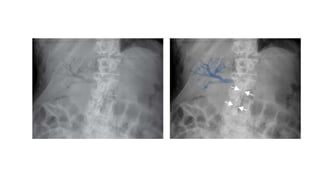

PORTAL VENOUS GAS

Branching dark lines within the periphery of the liver.

High mortality rate.

Main causes:

1. ischaemic bowel (most common)

2. necrotising enterocolitis (NEC) – most common in infants.

3. severe intra-abdominal sepsis